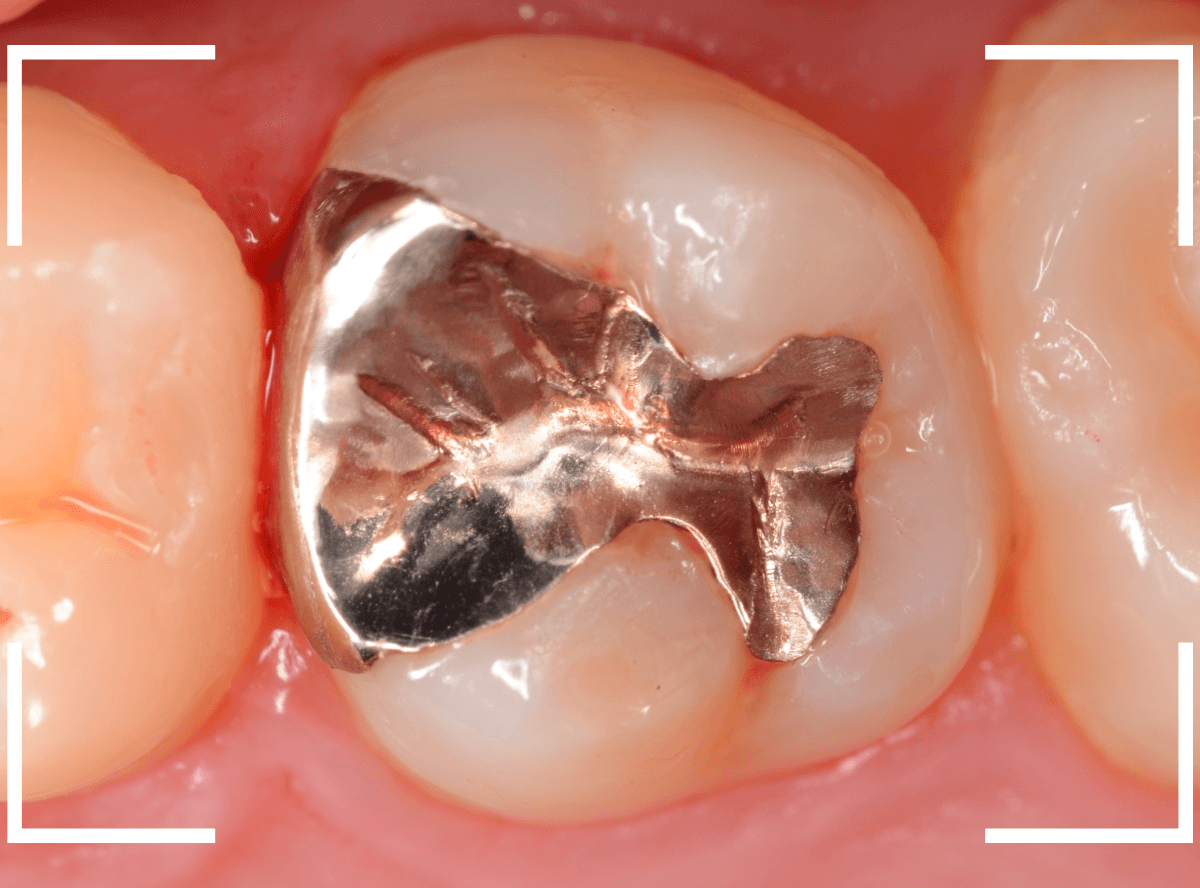

Case.4 2年間メンテナンスを中断している間に、深く虫歯が進行!

定期メンテナンスを2年間中断後に、来院された患者さんです。

見た目は手前の歯との間の小さな虫歯に見えますが、

「普段は痛くない」

「食事の時に物がつまる」

「物がつまった時に噛むと痛い」

・・・と、自覚症状は乏しいが、実際は大きな虫歯の場合の症状あるあるの訴えでした。

レントゲン写真で虫歯の状況を確認します。

赤い線が虫歯の部分、青い線が歯の神経の部分です。

思った通り、入り口の小さなすき間の中は、神経まで達してしまいそうな大きな虫歯になっていました。

歯を削り始めると、すぐに大きな穴が出てきました。

ある程度虫歯を除去したところで、う蝕検知液で染め出してチェックします。

まだまだ虫歯が残っていますね。

取り残しがないように、しっかり除去する必要があります。

虫歯を全て除去したところです。

神経が少し見えるところまで虫歯が進行していました。

神経を保護するお薬をつめた後、蓋をしてしばらく痛みが出ないか、経過観察します。

痛みが出て止まらないようでしたら、神経を除去する治療が必要になります。

定期メンテナンスを中断しなければ、このような状況にはならなかった事が本当に悔やまれます。

しばらく経過観察後、幸運にも特に症状なく経過しましたので、型どりをして、つめもの(メタル・インレー)で修復する事ができました。

この後、サボらず定期メンテナンスに来院いただくよう、念を押して治療終了となりました。